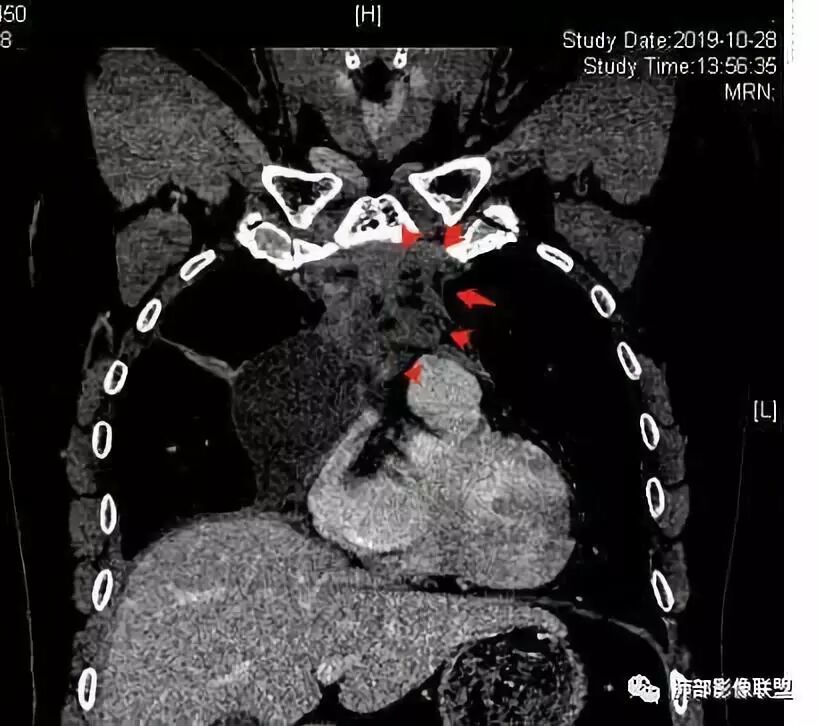

穿越七海的风:右前纵隔占位,恶性肿瘤,生殖来源?右肺实变是占位or肺不张?考虑为部分肺不张FeNo:右前纵隔占位,右肺结节,胸膜凹陷,小尾巴,右肺不张,考虑恶性杨旭华:恶性,前纵隔肿物,与血管关系密切,上腔静脉变窄,右肺野一元论考虑叶间裂增厚,恶性胸膜间皮瘤可能大小丽:到底是纵隔来源还是胸膜来源?我怎么倾向于胸膜来源,和叶间胸膜关系密切,而且纵隔内上腔静脉是向内侧推移。胸膜肿瘤(间皮瘤?SFT?)包裹性胸腔积液?马春平(张家港市一院胸外科):前纵隔占位,左无名受压,右大量胸腔积液可能是胸导管汇入处侵犯受压,考虑纵隔鳞癌孙冰伟:右上纵隔占位,也感觉和叶间胸膜关系密切,右侧胸膜局限性增厚,考虑恶性可能性大灵:前纵隔占位,血性胸水,胸膜凹凸不平,查见肿瘤细胞,结合免疫组化考虑胸腺癌。鉴别胸膜间皮瘤。采莲:右前上纵膈旁可见类圆形肿块,纵隔血管内移,感觉来源于胸膜,肿块内密度低,似水样密度,右侧胸膜广泛增厚,少量胸腔积液。心包少量积液。考虑胸膜间皮瘤,鉴别肺癌并胸膜转移?水晶石头:患者中年男性,胸闷15天。有“高血压、慢性肾小球肾炎”病史。查肿瘤标志物正常,胸水提示渗出液,胸水病理查见瘤细胞。胸部CT:右肺上叶后段结节、斑片影,见胸膜牵拉、包裹积液及部分纤维条索灶,似见卫星灶,右侧胸膜增厚。前纵隔脂肪密度增厚,右侧可见类圆形低密度(液体)肿块,边缘光滑。综合考虑右肺腺癌并胸膜转移,结核可能。周太狼:考虑纵隔胸膜来源肿瘤,恶性,胸膜间皮瘤伴转移?徐飞:中年男性,影像为右侧胸腔及叶间积液,叶间胸膜增厚轻度强化。前纵隔右侧心缘旁团块,可见坏死。胸水见癌细胞,综合考虑恶性,胸腺癌伴转移。小赵:中年男性,血性胸水,常规查见癌细胞,李凡他实验阳性。胸部CT示前纵隔见不均匀密度影,与邻近大血管分界不清,囊变坏死明显,增强扫描呈不均匀强化,心包及右侧胸膜增厚,并心包及右侧胸腔少量积液。综合考虑胸腺癌。右肺中叶病变周围见多发纤维条索,支气管部分进入病灶,考虑炎性病变。流心明智:患者,男性,50岁。胸闷15天。高血压20年,慢性肾小球肾炎15年。肿标正常,胸水提示渗出液,胸水查见癌细胞。胸部CT:右肺肿块影,斑片影,索条影,可见胸膜牵拉、多发包裹积液,纵隔上腔静脉受累,心包受累。综合考虑:ROSE似腺?考虑右肺腺癌并胸膜转移,心包受累。鉴别胸腺Ca、淋巴瘤,纵隔病变不懂,等老师们精彩分析。王秀仙:前纵膈囊实性肿块,与纵膈分界不清,心脏大血管及上腔静脉受压向内后移,右侧后胸膜、侧胸膜增厚,右侧叶间裂不规则增厚,心包积液,根据腔静脉移位情况,考虑纵膈胸膜来源恶性肿瘤,胸膜间皮瘤?鉴别胸腺癌并胸膜转移。高广飞:上纵隔占位,右侧叶间胸腔积液,需考虑恶性自信人生:多发囊实性病灶,包裹性积液,考虑胸膜来源 只是没有看到壁结节,恶性胸膜间皮瘤巴伟:前上纵隔占位,胸膜及心包结节,考虑胸腺瘤或癌,右肺病灶,先考虑陈旧炎性病变。Lenle董:前纵隔占位,部分边缘模糊,病灶内囊变?坏死?上腔静脉受侵,考虑胸腺癌;叶间片状影,强化明显,炎性考虑。常志强:前纵隔囊实混杂密度肿块,边界不清,实性部分强化明显,结合胸水内见癌细胞,考虑恶性肿瘤伴转移。飞鹰行动:前纵隔占位,软组织密度及囊性密度,实性部分密度均匀,致密,病灶与周围血管分界不清,增强后病灶强化有类似不温不火强化,部分血管受侵犯,右肺见肿块样病变及条索状病变,一元论,考虑淋巴瘤,二元论,考虑胸腺瘤B2—B3伴右肺病变。尽量一元论考虑,淋巴瘤可能。看图说话:右肺索条病灶,边缘膨隆,胸膜牵拉,考虑右肺癌伴胸膜转移。晨:前纵隔囊实性肿块,与纵隔分界不清,右侧后胸膜、侧胸膜增厚,右侧叶间裂不规则增厚,考虑纵隔胸膜来源恶性肿瘤,考虑胸腺癌并胸膜转移。丽:中年男性,前纵隔囊实性肿块,呈偏心性生长,临近大血管受压推移,增强后实性部分不均匀强化,心包可见条形积液,考虑胸膜来源恶性肿瘤,胸腺癌可能大。另右肺多发斑片状高密度影及实变密度影,实变影呈均匀强化,右侧胸膜局限性增厚,考虑炎性病变。小飞:右前纵隔囊实性占位,实性部分明显强化,右侧叶间胸膜增厚,右侧胸腔积液,心包积液,考虑恶性胸腺瘤!尘缘:支持恶性胸腺瘤(囊实性肿块,实性强化,且侵犯纵隔,脂肪间隙模糊)伴肺内及胸膜转移。浪迹天涯:考虑侵袭性胸腺瘤——胸腺前纵隔占位,周围脂肪间隙模糊不清。尘缘:不除外另一种可能:二元,肺内腺癌合并胸膜转移,纵隔的畸胎瘤可能。一米阳光:晨读中年男性,右肺结节影,叶间裂及胸膜增厚牵拉,右侧胸水。心包多发结节改变。胸水查见癌细胞。考虑,腺癌并转移。鉴别,胸膜间皮瘤并转移前纵隔囊实性占位,二元考虑。心灵鸡汤:老年男性,右肺中叶外段长条状软组织密度影,边缘膨隆,邻近胸膜牵拉,部分胸膜有栽脏,右中叶外侧段支气管堵塞,常规考虑恶性肿瘤,腺癌可能,结核、鳞癌不除外,另右肺上叶斑片影,小叶性肺不张?右前纵隔囊实性不规则形密度影,其内见部分脂肪样极低密度影,与邻近血管边界不清,心包外膜有侵犯,增强未见纵隔窗平扫,实性及分隔见增化,其内低密度影未强化,考虑低度恶性纵隔肿瘤,间皮瘤可能,畸胎瘤、淋巴瘤待排,建议支气管镜及穿刺活检。曹志勇:右前纵隔考虑来源于胸膜的恶性肿瘤,右肺内病灶考虑鳞癌,二元德芙~云味:中年男性,右肺见结节、斑片影,右侧包裹积液、胸膜牵拉,纤维条索,前纵隔囊性占位,考虑腺癌、并转移。欧阳英:右前中纵隔囊实性肿块及右肺内结节灶,支持恶性肿瘤,胸腺癌并肺内转移可能张延军:前纵隔见不规则软组织影,密度不均,右侧缘见囊变区,纵膈及侧胸壁胸膜增厚,增强呈不均匀强化,右肺中叶见结节灶,近段支气管阻塞,叶间胸膜不规则增厚,考虑1:右肺中叶腺癌伴纵膈及胸膜转移;2:前纵膈侵袭性胸腺瘤并胸膜侵犯,中叶炎性改变?彭君:老年,前纵隔占位 ,坏死边缘清, 侵犯心包 右侧胸膜及叶间胸膜结节 ,少量胸水, cea不高 ,考虑恶性, 间皮瘤可能 ,转移待除外。毛勤香:恶性没问题,胸水查见癌细胞,一元还是2元,右肺中叶肿块,边缘毛糙,局部似有毛刺,周围有粘连,右侧胸膜腔少量积液,胸膜增厚多发结节,含叶间裂结节,纵膈脂肪间隙模糊,纵膈胸膜增厚,心包增厚积液,右前那个类圆形低密度肿块,纵膈血管内移,我考虑胸膜来源可能性大,综合考虑,一元肺腺癌并多发转移,二元考虑胸膜间皮瘤并多发转移,肺内炎症不张。

南边:大家看看前纵隔的病灶,符合肿瘤吗脂肪,周围密度增高

三个石头:比较散;像炎症的蔓延生长南边:是,这些看着心里不踏实觉得把这个纳入肿瘤去考虑是否合适总觉得边缘收缩的、散在的朝周围蔓延;中央还跨过脂肪,朝对侧胸膜蔓延把这个与囊性病变连到一起去考虑是否还需要斟酌一下因为这个就方向差异大了南边:连在一起,囊实性,边界不清,自然考虑恶性:如果独立,囊张力高、边界清楚,间隔,自然朝良性考虑:

Coke with ice:囊性部分考虑包裹性积液?南边:不是积液;有间隔;张力高;而且位置有些特殊

大家仔细看看积液中的游离气体;

不是支气管,是积气;是穿刺进去的;

我认为囊张力高,积液中的气体均在周围,外侧、下方,囊内有间隔:各腔密度不一致;提示:囊腔属于前纵隔,不是包裹性积液;现在的问题:囊腔与内侧的病灶是否是一体的

南边:我总觉得这个纵隔内不像是一个肿块的改变,扁平,周围蔓延:有符合炎性的的特点,或者肿瘤的侵犯;但是肿瘤的侵犯,不大符合,实性部位的边缘过于柔和,没有毛糙的侵犯边缘。

2、前纵隔内病灶囊实性混杂密度病灶,囊性病灶主要位于右侧,张力较高,有分隔影,囊壁右侧缘光整,病灶左侧实性部分边界不清明显强化,病灶肺瘤交界面大部分边界清楚,部分模糊。